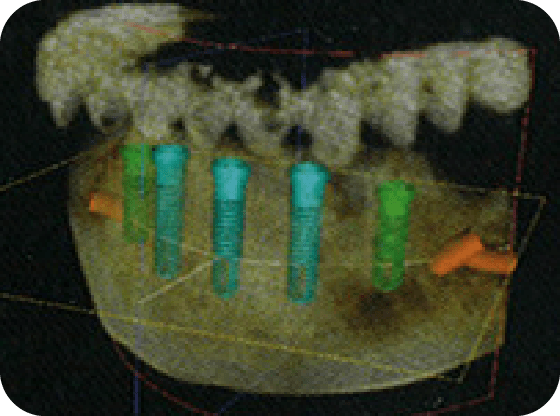

2 精密検査

最先端の設備を使った精密検査を行い、患者様の口腔内をより詳細に確認させていただき、治療が可能かどうかを診断します。より正確・安全なインプラント治療を実現するために、当院では歯科用CT(コンピューター断層撮影)を導入しています。撮影されたCT画像データはコンピュータを用いて分析し、術前の診査・診断ならびに治療計画に役立てます。

はい、インプラントは安全な治療です。当院ではより安全、正確な治療をするため、必ず術前に歯科用CTにて3次元的にアゴの状態(骨幅や神経まで距離など)を精密検査します。